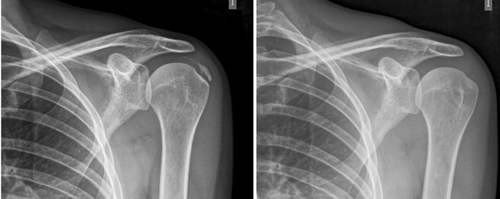

Resultados: Edad media: 54,6 años (n = 138); mujer (73,1 %; n = 101); proporción mujer/hombre 3: 1; tendón supraespinoso (94,6 %; n = 124); subescapular (5,4 %; n = 14); hombro izquierdo (55,1 %; n = 76), hombro derecho (44,9 %; n = 62); bilateral 1,4 % (n = 2); diestros 96,3 % (n = 133); antecedentes personales: tabaquismo (19,5 %; n = 27), diabetes (7,2 %; n = 10). El tiempo de enfermedad promedio fue de 6,08 meses. Dolor agudo-subagudo (menos de 3 meses) 47,1 %; (n = 65), dolor crónico (más de 3 meses) 52,9 % (n = 73). Tipo radiológico: formativo 75,3 % (n = 104), resortivo 24,7 % (n = 34). Número promedio de sesiones: 20. Complicaciones del tratamiento 2,8 % (n = 4): intolerancia/eritema/quemadura. Ocupación: administrativo 39,8 % (n = 55), trabajos manuales 60,2 % (n = 83). El dolor inicial EVA de 7,3 puntos disminuyó significativamente (p = 0,0000) después del tratamiento a 2,7. El tamaño promedio inicial de las calcificaciones fue de 10,7 mm y disminuyó significativamente (p = 0,0000) después del tratamiento a 3,8 mm. Cambio de calcificación: tasa de éxito/curación 55,7 % (n = 77), tasa de mejora 20,2 % (n = 28); tasa de fracaso del 23,9 % (n = 33). La limitación funcional disminuyó de un 10,8 % a un 2,1 %.

Average initial pain 7.3 points (VAS scale), significantly decreased (p = 0.0000) post treatment to 2.7. Initial average size of calcifications 10.7 mm and significantly decreased (p = 0.0000) post treatment to 3.8 mm. Change of calcification: success/cure rate 55.7 % (n = 77), improvement rate 20.2 % (n = 28); failure rate 23.9 % (n = 33). Functional limitation decreased from 10.8 % of patients to 2.1 %.